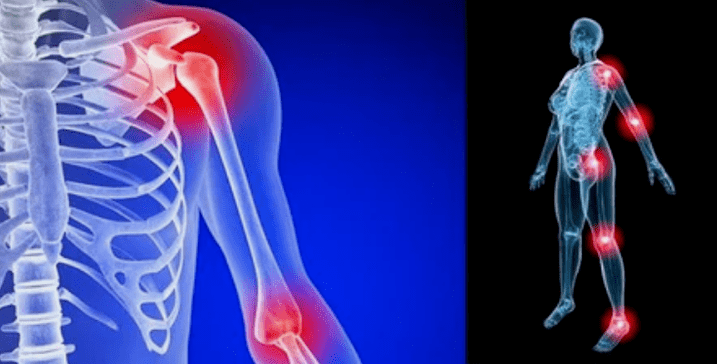

The manifestations of the disease are very small depending on the localization, often the signs are reflected on the knees, shoulders and hip joints, due to the high load.

- Pain.They have low severity at the initial stage, with increased sensation.Initially, the joints were only damaged after waking up, after a warm feeling, feeling disappeared.Over time, the pain appears at night, they are very disturbed during and after prolonged walking, running, etc. in the final stage, the pain syndrome pursues a person at all times;

- Swelling with red.It is localized near the disease, which shows a process of inflammation and progression of the disease.The doctor understands that the interpretation shell is affected, which causes liquid accumulation and increased pain;